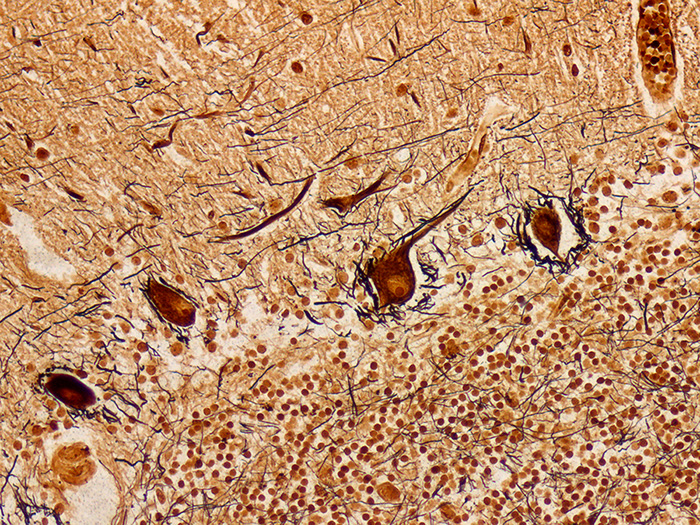

Newcomer Supply Bielschowsky Control Slides are for the positive histochemical staining of nerve fibers, neurofibrils/tangles, senile plaques and axons, instrumental in the diagnosis of Alzheimer’s disease and other neurological disorders.

RESULTS:

| Senile plaques, neurofibrils/tangles | Dark brown to black |

| Neurons | Dark brown |

| White and gray matter | Yellowish brown |

| Nerve fibers, axons | Brown to black |